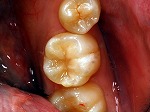

~臼歯術前~

コンポジットレジン充填

~臼歯術後~